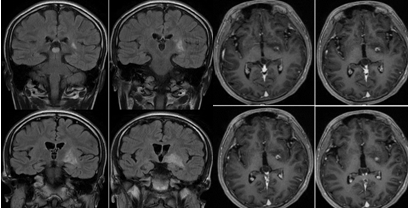

女性,31岁,头痛半月余,加重1周于于2020年3月25日入院。 患者半个月前出现头痛,多睡眠中痛醒,持续数分钟,1次/天。1周前头痛症状加重,呈周期样发作(头痛持续数分钟,缓解数分钟),间歇半个小时至1小时不等,持续时间及发作频率渐增加,约7-8次/天,基本卧床状态(除吃饭,二便),从坐姿到站姿时头痛明显,睡觉时头痛减轻,多痛醒。3天前患者出现视物不清,看远处物体时明显,视力损害逐渐加重。病程中患者有自觉发热,自测体温不高,无恶心呕吐。

2020年4月7日复查颅脑核磁:

腰椎穿刺,脑脊液压力450mm。脑脊液常规:有核细胞:23×10^6/L,淋巴细胞96%。脑脊液生化:蛋白0.27g/L,氯123mmol/L,葡萄糖:3.48mmol/L脑脊液涂片:墨汁染色见新型隐球菌。脑脊液隐球菌荚膜抗原阳性。

答案:隐球菌性脑膜炎。由扩大的VR间隙融合而成的胶质假性囊肿,直径>5mm,单发或多发,可聚集成簇状囊肿。病变分布与VR间隙扩大分布一致,常位于基底节区,呈对称性分布,为隐球菌荚膜所产生的粘液,胶状物质充填而扩张,形成的小囊腔,含大量隐球菌,呈肥皂泡状,具有一定特征性。 呈类圆形,边界清楚,T1WI呈低或稍低信号,T2WI呈稍高或高信号,增强可强化(增强被认为是免疫完整宿主的慢性炎症反应),弥散可受限。